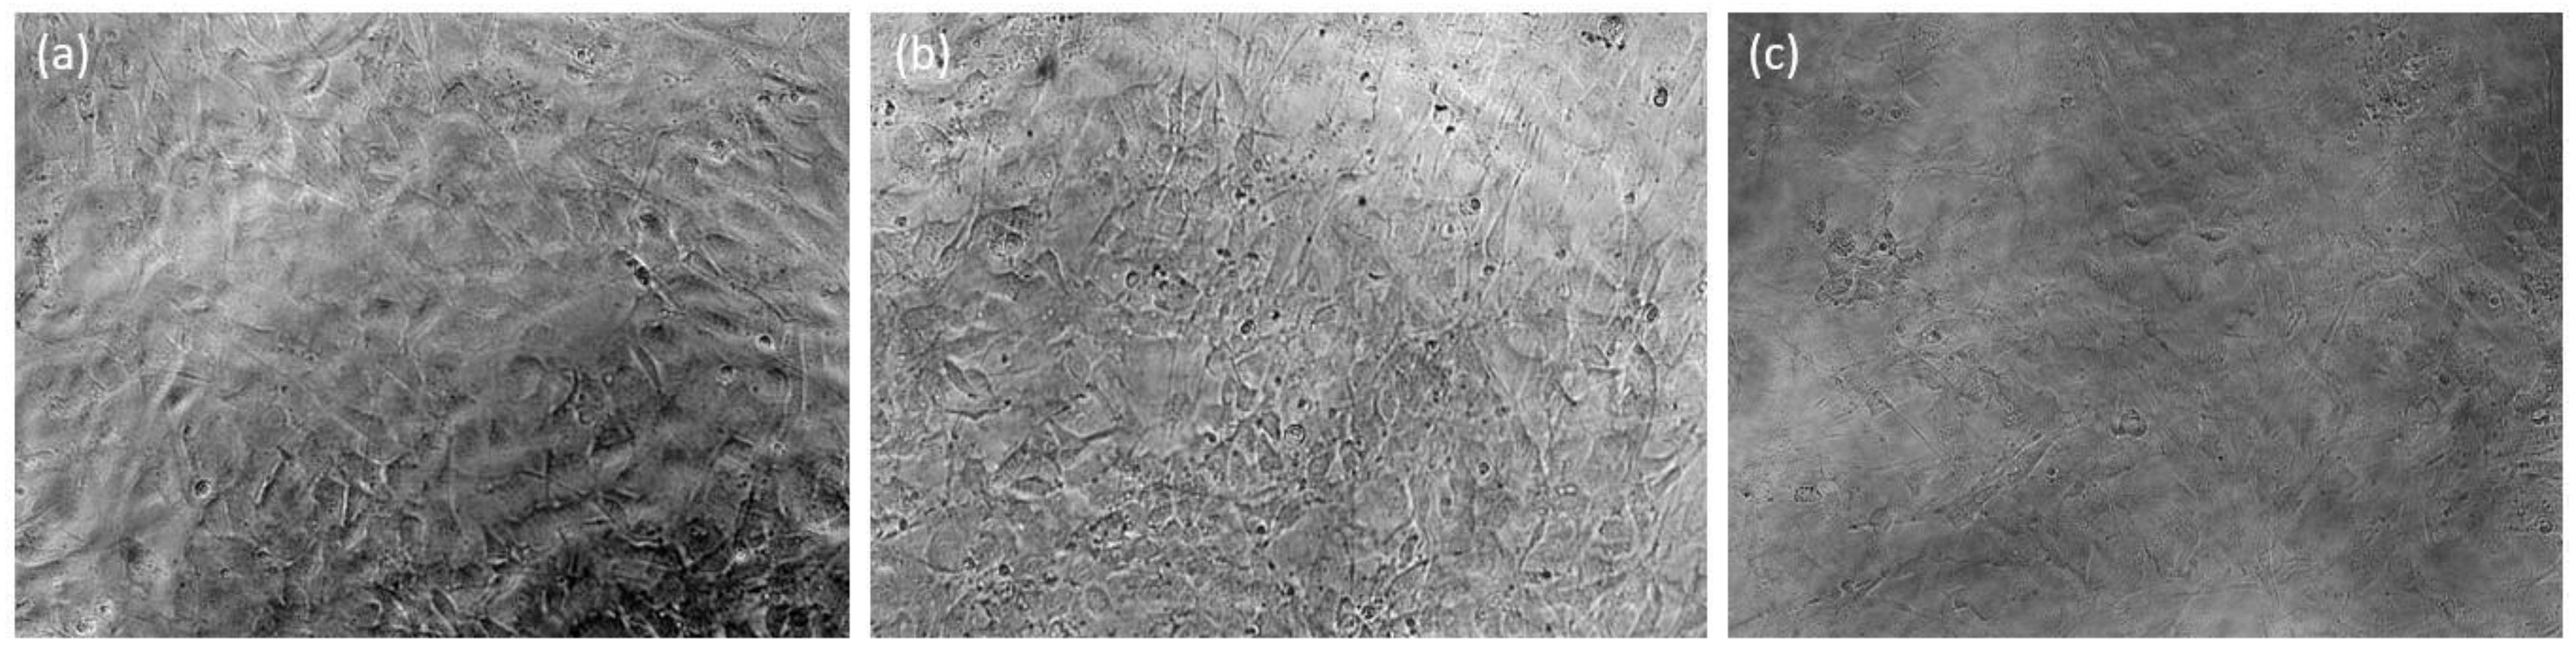

On Days 1, 5, and 7, both NETA-loaded and drug-free segments exhibited non-significant impact on the cellular viability, when compared to the negative control [p = 0.092, p = 0.09 (Day 1), p = 0.863, p = 0.966 (Day 5), p = 0.602, p = 0.146 (Day 7) for NETA-loaded and drug-free segment, respectively]. On Day 3, both segments exhibited significant differences compared to the negative control (p = 0.005, p = 0.009, for NETA-loaded and drug-free segments, respectively). Additionally, the results showed that there are no statistically significant differences (p > 0.05) between the NETA-loaded and the drug-free segment on the cellular viability throughout the 7-day study period. Adhering to regulatory guidelines, a relative cell viability exceeding 70% compared to the control group (100%) implies non-cytotoxicity of the materials [64,65]. The MTT assay results on the NIH/3T3 cell line, as illustrated in Figure 11, affirms the cytocompatibility of the prepared optimized drug-free and NETA-loaded segments. Figure 12 further represents microphotographs of NIH/3T3 on Day 7 after treatment for the negative control, NETA-loaded segment extract, and drug-free segment extract, which further demonstrates the cytocompatibility of the optimal NETA-loaded formulation.

Figure 12.

Micrographs of NIH/3T3 cells after 7 days treatment at 20× for (a) the negative control in cell culture media, (b) the NETA-loaded segment extract, and (c) drug-free segment extract (scale: 1 cm = 100 µm).